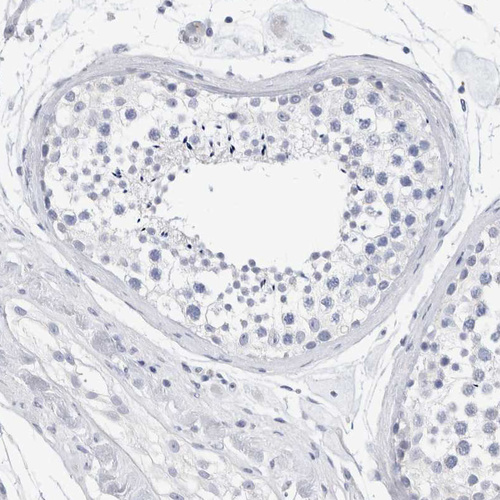

Immunohistochemistry analysis in human kidney and testis tissues using HPA024575 antibody. Corresponding SLC22A12 RNA-seq data are presented for the same tissues.